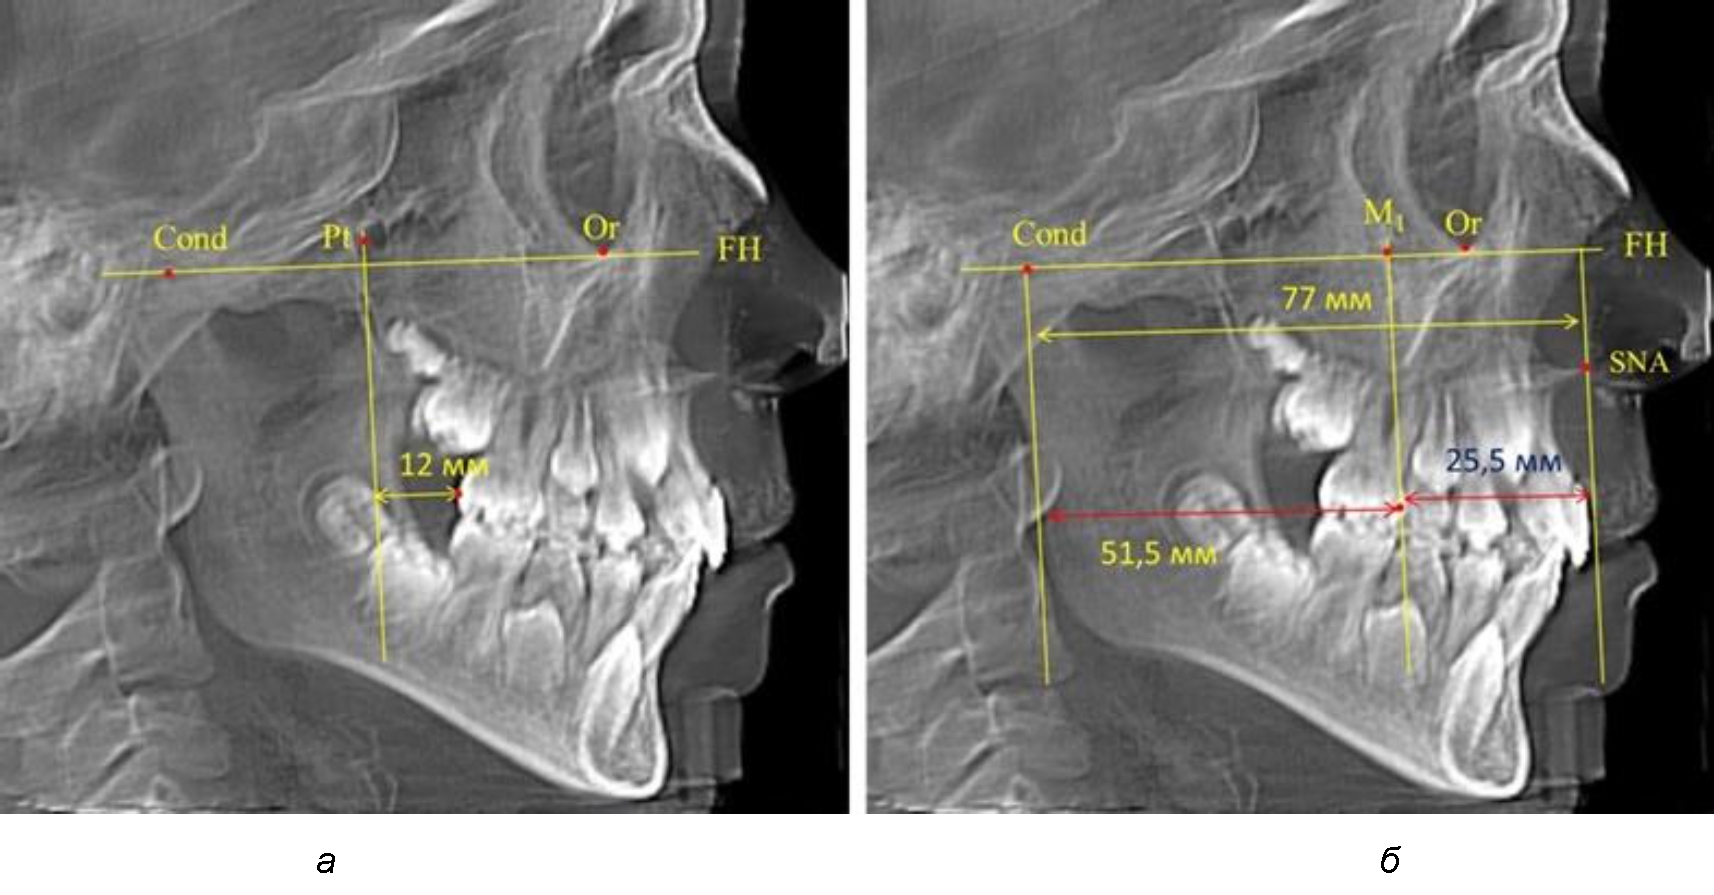

Находили положение точки Pt, которая располагалась на пересечении нижнего края круглого отверстия и задней стенки крыловидно-верхнечелюстной щели, и перпендикулярно к Франкфуртской горизонтали проводили крыловидную вертикальную линию, которую принято обозначать как плоскость PTV. Расстояние от крыловидной вертикальной плоскости PTV до дистальной поверхности верхнего первого постоянного моляра определяло его положение, которое, по мнению R. E. McDonald, соответствовало возрасту пациента, увеличенному на 3 мм.

При проведении анализа к Франкфуртской горизонтали проводили передний и задний перпендикуляры. Передний спинальный перпендикуляр проходил через выступающую точку передней носовой ости (spina nasalis anterior – SNA), а задний суставной перпендикуляр опускали из кондилярной точки Cond. Молярный перпендикуляр проводили через медиальную поверхность первого постоянного моляра. Указанная вертикаль отделяла замещающие зубы постоянного прикуса от добавочных зубов (постоянных моляров), что вполне логично для анализа положения первых постоянных моляров в гнатическом комплексе (рис. 1).

Рис. 1. Метод определения положения первых верхних моляров по Ralph E. McDonald (а) и по предложенному методу (б)

Анализ проведенного исследования рентгенограмм показал существенную вариабельность практически всех линейных показателей. У молодых людей с физиологическим прикусом постоянных зубов расстояние от крыловидной вертикальной плоскости PTV до дистальной поверхности верхнего первого постоянного моляра в целом по группе составляло (18,37 ± 3,62) мм. Обращает на себя внимание большая ошибка репрезентативности из-за разницы между максимальными и минимальными значениями.

Среди анализируемых рентгенограмм минимальное значение расстояния по методу R. E. McDonald было 12 мм, а максимальное достигало 25 мм, что, по нашему мнению, обусловлено вариабельностью сагиттального размера гнатического отдела лица.

Среднее расстояние между суставной (кондилярной) и спинальной вертикалями в анализируемой группе составило (89,12 ± 2,8) мм. При этом сагиттальный размер в среднем составлял (58,74 ± 1,57) мм, а передний размер был (30,41 ± 1,02) мм. Несмотря на вариабельность размеров и большую ошибку репрезентативности, относительно стабильным показателем было отношение сагиттального размера гнатического комплекса к заднему отделу, которое составляло в среднем 1,5 ± 0,06.

Таким образом, для прогнозирования оптимального положения первых постоянных моляров наиболее целесообразным методом явилось использование относительного показателя, что подтверждено при анализе рентгенограмм с минимальными и максимальными значениями по методу R. E. McDonald.

Так, при расстоянии от крыловидной вертикальной плоскости PTV до дистальной поверхности верхнего первого постоянного моляра в 13 мм сагиттальный размер гнатического отдела был 82 мм. При этом отношение кондилярно-спинального расстояния к кондилярно-молярному размеру (54,5) было близким к коэффициенту 1,5, что представлено на рис. 2.